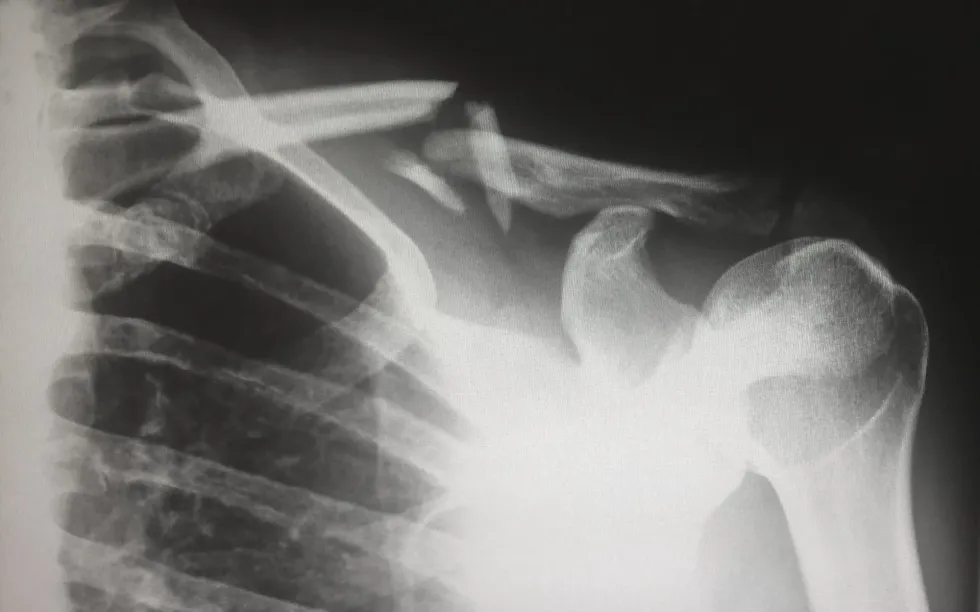

The technology was primarily deployed to locate any fractures or infections in bones, cavities in teeth, or for basic evaluation of certain parts.

An arthrogram is useful to find arthritis with joint alterations, malignancy in bones, and osteoporosis by measuring bone density. Pneumonia, lung cancer, and tuberculosis can be identified through chest x-rays. Lymphoma in breasts with mammography, heart issues with any conversion in blood flow, and digestive tract issues like kidney stones, and accidentally swallowed objects can also all be identified.